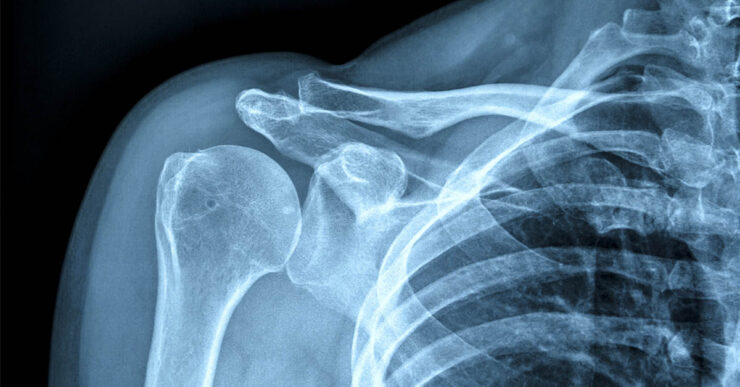

Osteoporosis often advances silently, gradually weakening bones until a severe fracture reveals the damage.

This disease primarily affects older people, especially women, and is responsible for millions of fractures around the world each year.